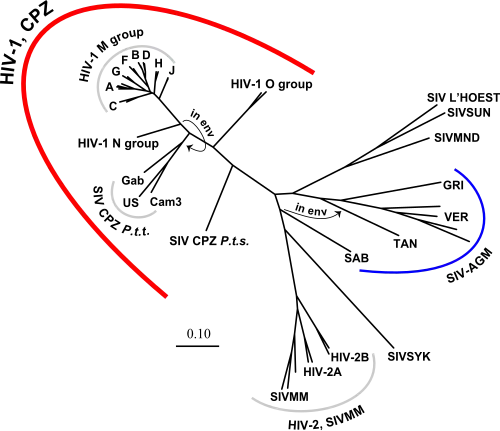

L'arbre phylogénétique du VIH est en 2019, le suivant :

Le VIH est un virus qui a une très importante variabilité génétique et présente ainsi une extrême diversité. Deux types ont été identifiés :

- VIH-1, le plus présent dans le monde ;

- VIH-2, moins contagieux que VIH-1. Il sévit principalement en Afrique de l'Ouest. Il comprend le VIH-2A et le VIH-2B.

Au sein de chaque type existent plusieurs groupes qui, à leur tour, comportent des sous-types.

Depuis 1998, le VIH-1 est classé en trois groupes[81] auquel s'ajoute un quatrième découvert en 2009[82] :

- groupe M (pour major group) ;

- groupe O (pour outlier group) ;

- groupe N (pour non-M, non-O group) ;

- groupe P.

Les types M et N du VIH-1 sont proches du VIScpz infectant le chimpanzé et correspondraient chacun à une transmission indépendante du chimpanzé à l'humain[83]. Les types O et P du VIH-1 sont proches du VIS infectant le gorille (VISgor)[82].

Le groupe M prédomine largement avec plus de 40 millions de personnes contaminées, contre un peu plus de 500 pour le groupe O et seulement 7 pour le groupe N[83]. Non seulement le groupe M est de loin le groupe le plus important en nombre de personnes contaminées, mais il est également celui qui est le plus répandu de par le monde, en étant présent sur tous les continents, alors que les autres groupes sont uniquement présents en Afrique centrale[84].

Le groupe M comprend neuf sous-types ou clades (de A à D, de F à H, J et enfin K). S'ajoutent plusieurs formes recombinantes (en anglais circulating recombinant form ou CRF), qui ont pour origine la multiple infection d'une cellule par des sous-types différents, ce qui entraîne des mélanges dans le génome viral.

Les sous-types et formes recombinantes du groupe M ne sont pas réparties uniformément sur toute la planète. Ainsi, en Europe, dans les Amériques et en Australie, c'est le sous-type B qui est le plus présent, alors qu'en Afrique c'est, selon les régions, le A et le C et, en Asie, toujours selon les régions, les groupes C et E[85].

La variabilité du génome viral n'est pas la même pour tous les gènes, certains sont plus enclins à varier que d'autres. C'est ainsi que le gène env est le plus variable (c'est justement lui qui code les protéines de surface gp41 et gp120), alors que le gène pol est le plus conservé[93].

- Origines multiples

La multiplicité temporelle des passages du VIScpz à l'humain est la raison de l'existence des différents groupes du VIH-1. Il en est de même pour le VIH-2, dont l'ancêtre est le VISsmm.